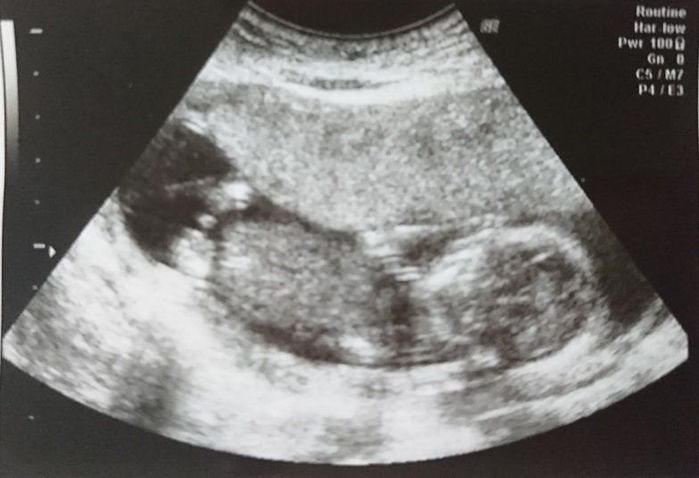

妊娠11週目のエコー写真 おなかが膨らみ始めました

超音波で赤ちゃんがおなかの中で元気に動いているのが分かりました。おなかが膨らみ始めたので、普段着る物と会社用のマタニティー服を準備しました。真冬なのでコートで隠せて、周りの目をそれほど気にしなくても良かったのは助かりました。